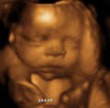

32 недели

И так наступила 32-я неделя и мы с мужем отправились на узи которого с нетерпением так долго ждали. В этот раз многое было привычным, теперь не было страшно смотреть на экран или что-то спросить. Все было на столько интересно, что даже нехотелось уходить.

Теперь малыш стал совсем большим,его очень хорошо видно и абсолютно понятно, что это непросто эмбрион, а настоящий человек!!! Сначала нам показали его ручки и ножки, померили длину косточек. Читать далее»